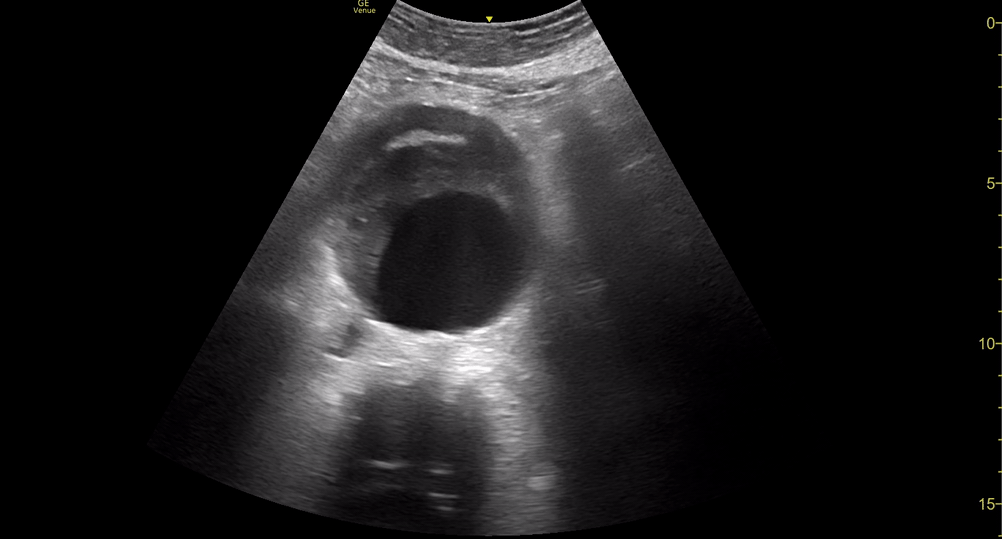

AAA

AAA GALLERY

AORTIC ANEURYSM

In adults, the normal anteroposterior aortic diameter is less than 2 cm, and 3 cm or more is considered dilated. The diameter of the common iliac arteries should not be more than 1.5 cm. Most AAAs occur below the renal arteries. As an aneurysm becomes larger it will dilate faster, leading to a greater risk of rupture. This risk remains low if the diameter is less than 5 cm. By contrast, there is a clear tipping point after surpassing 5.5 cm, as the annual incidence of rupture grows from <1% to 9.4% (5)

To rule out AAA the entire abdominal aorta should be visualized, including a minimum of three transverse images (proximal, middle and distal) and a longitudinal image. All images should be measured from outer to outer wall and saved as backup.

Once the aorta is identified, measure its diameter from outer to outer wall, as inner wall measurements may underestimate the diameter due to mural thrombus (false negative). While maintaining the transverse orientation, slide the probe distally until the aortic bifurcation and measure the diameter at its middle and distal portions. Then, rotate the probe to the longitudinal position, which is needed to identify saccular aneurysms. Attempt to obtain a view of the aorta that includes the origin of the coeliac trunk or SMA, and measure the AP diameter. Remember, AAA is not ruled out unless the entire length of the abdominal aorta can be visualized and measured.